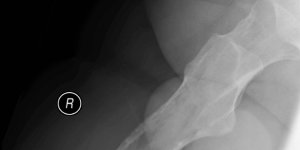

Hip Osteonecrosis | Cases

Published on Jan 20, 2021

59 ♂ B/L groin pain. 10/10 VAS Initially started on the left side like lateral hip pain. Had 2 steroid injections for lateral hip pain. Uses walking stick. Painful with weight bearing, getting in / out of car. No spinal symptoms. Recent X-ray NAD Exam Antalgic gait Pain deep in groin Hip flexion limited to 90° B/L Minimal internal and external [...] Read more